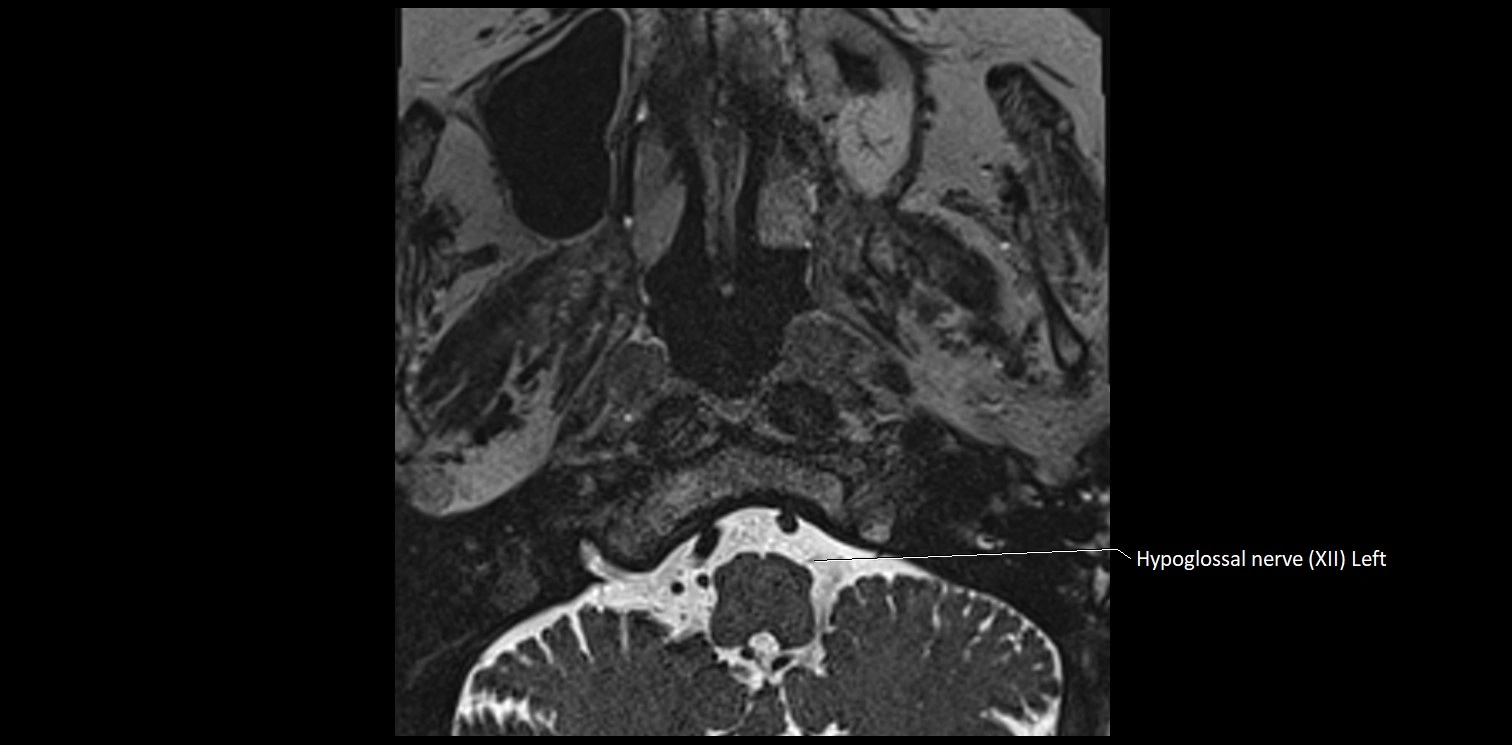

MRI Appearance

• The abducens nerve is a small, thin, linear structure

• Best visualized on high-resolution T2-weighted 3D MRI sequences (e.g., FIESTA or CISS)

• Seen as a hypointense (dark) line running from the brainstem at the pontomedullary junction, traversing the prepontine cistern, and entering Dorello’s canal under the petrosphenoidal ligament, then into the cavernous sinus, and finally the orbit

• May be challenging to visualize in standard MRI due to its small size

• Pathology may be inferred by absence, displacement, or enhancement of the nerve

MRI images

image